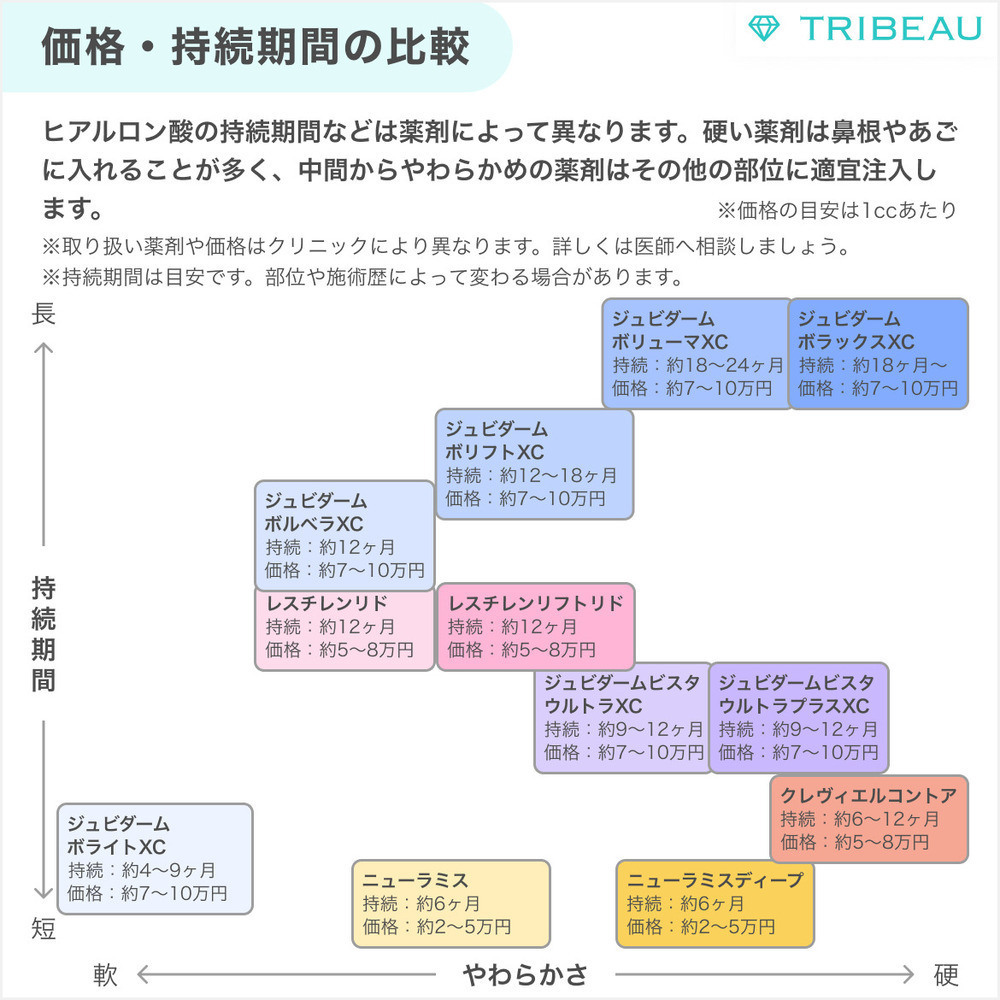

使用する薬剤は「チャウムスタイルプレミアム」です。

弾力性に優れたヒアルロン酸なので、おでこをきれいにボリュームアップできます。

個人差はありますが、効果の持続期間は1年ほどです。

・日本国内において、医薬品医療機器等法上の承認は取得していません。 ・医師等が個人輸入により入手したものです。未承認医療機器については「個人輸入において注意すべき医薬品等について」もご参照ください。 ・同一の成分や性能を有する他の国内承認医薬品等はありません。 ・韓国MFDSに承認されています。